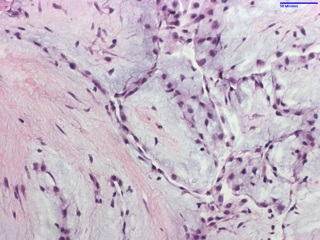

Histologically, they are composed primarily by collagen and elastin at the base with abundant mucopolysaccharide stroma, and outer endothelium expressing vimentin, factor VIII and CD34. The vasculature is minimal while myxomas (the main differential) are highly vascular lesions with typical “myxoma” cells and very rarely occur in heart valves.